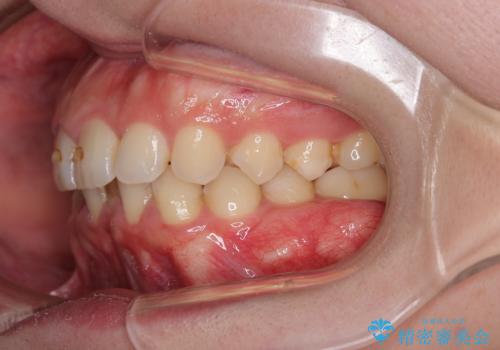

- 下の歯のがたつきを主訴に来院されました。

下の歯のがたつきと右の奥歯の噛みあわせ改善するために治療計画を立てることにしました。

右側臼歯部の咬合改善のために、臼歯部のみ部分的なワイヤー矯正を行い、咬合改善がみられてからインビザラインにて全体的な矯正を行なっていく治療計画を立てました。